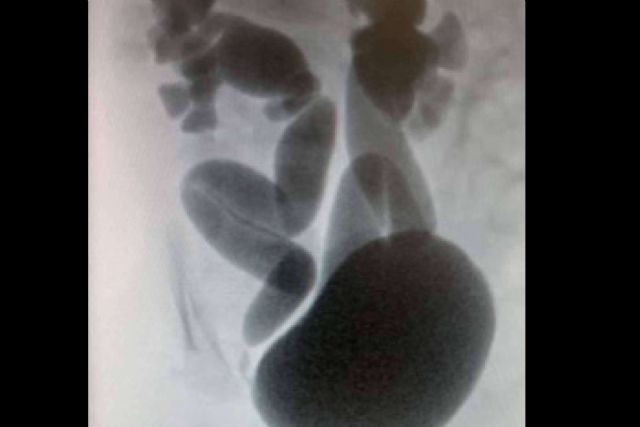

El diagnóstico del reflujo vesicoureteral en recién nacidos se realiza mediante pruebas especializadas, siendo la cistouretrografía miccional (VCUG) una de las más comunes. Esta prueba permite observar el reflujo de la orina y clasificar el grado de severidad, que va desde el I hasta el V. El Dr. Daniel Cabezalí señala que esta clasificación es fundamental, ya que influye directamente en la elección del tratamiento, que puede variar desde la vigilancia activa hasta la cirugía en los casos más graves.

El VCUG se recomienda especialmente si el recién nacido ha sufrido infecciones urinarias recurrentes o si se ha detectado hidronefrosis, una dilatación de los riñones durante las ecografías prenatales. El Dr. Cabezalí subraya la importancia de un diagnóstico preciso y temprano para evitar complicaciones mayores, como infecciones renales que pueden llevar a la cicatrización del tejido renal y, en casos extremos, a una disminución de la función renal.